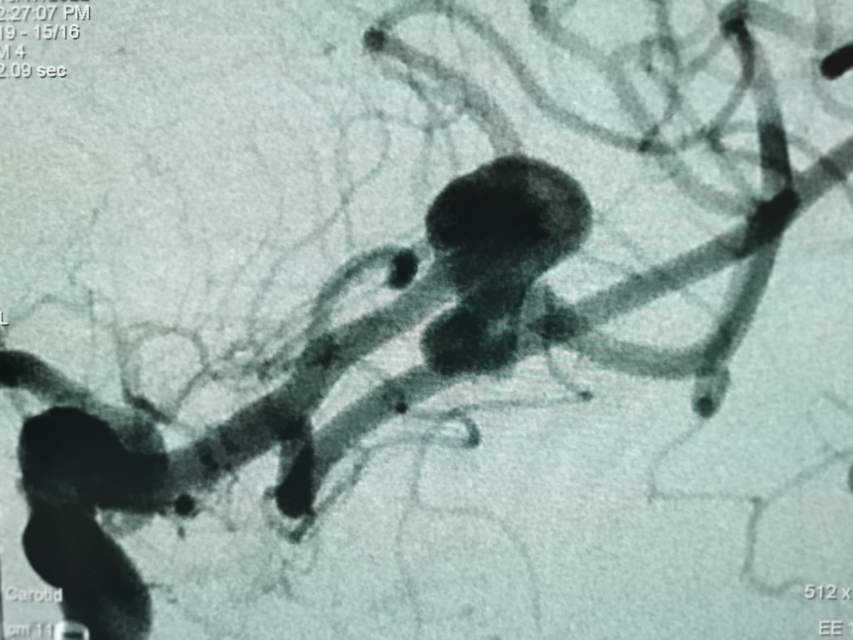

福建中年女性,近期在外查出“颅内动脉瘤”,经推荐转来我院诊治。患者的颈内动脉通路迂曲,动脉瘤也位置奇特,解剖复杂,动脉瘤远近段的血管弯弯绕绕,重重叠叠,眼花缭乱,难以兼顾找到最佳位置。最终克服困难,将“基底型”动脉瘤改变为“侧壁型”动脉瘤,顺利给予治疗……